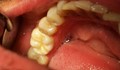

Състоянието на устата говори за вашето здраве